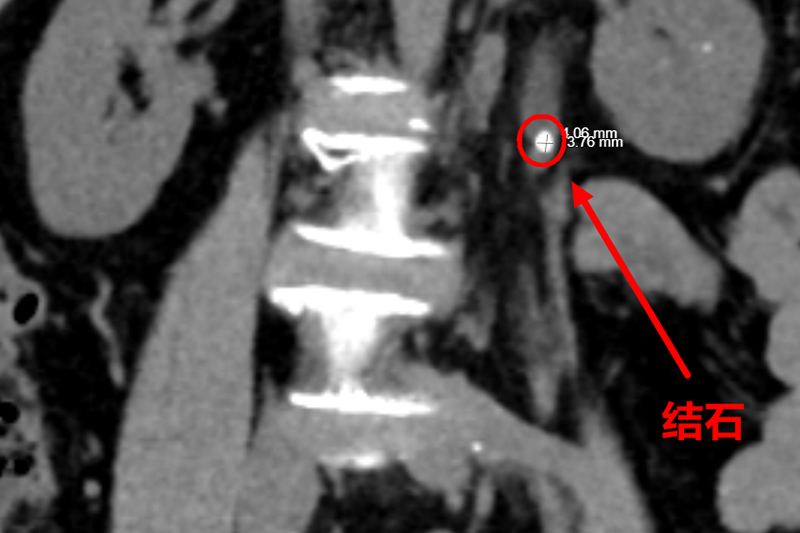

急诊CT更是直接揪出了“元凶”:一颗直径4mm的结石嵌顿在左侧输尿管上段!